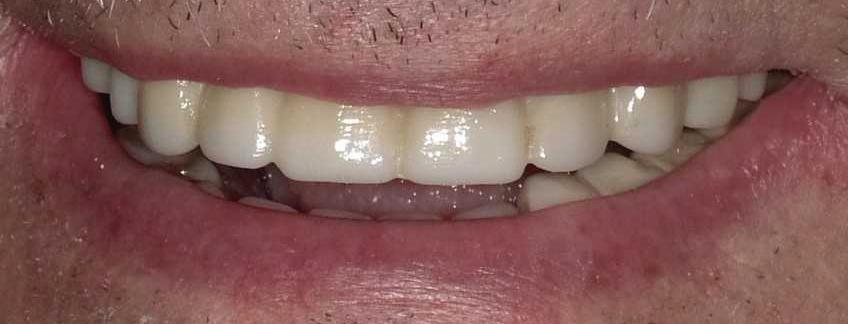

Can just four implants replace all of the teeth on the top or the bottom of your mouth? Thanks to advances in dental implant technology, that answer is a resounding yes.

Believe it or not, tooth loss is extremely common among adults, especially as we age. In fact, more

than 35 million people in America are missing all of their upper and/ or lower teeth. Rather than living with the discomfort and hassles of dentures, many people are opting for what is called “all-on-four” dental implant restoration.

All-On-Four: One Full Arch Of Teeth, Four Dental Implants

To fully understand this remarkable technique for replacing teeth, you should first understand what a dental implant is. An implant is a small titanium screw that fits inside your jawbone and replaces the root-part of a missing tooth. Minor surgery is required to insert the implants. Once the implant is in place, a crown is attached to give you a highly realistic-looking and functional prosthetic tooth.

Here’s where it gets really interesting: You do not need a dental